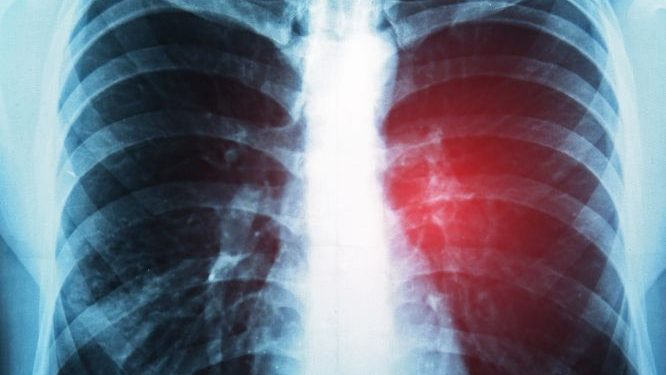

Stage 4 adenocarcinoma cancer is classified as metastatic because it has spread from the lung to other sites in the body, such as other lungs, bones, and the brain. The overall survival rate for people who have this type of lung cancer is about 8%, according to the National Cancer Institute’s Surveillance, Epidemiology, and End Results Program database.

The survival rate for a person with metastatic lung cancer depends on several factors, including the type of cancer and where it has spread, according to Moffitt Cancer Center. If a person’s cancer has only spread to one site, such as the brain, they may be able to be treated and even cured with surgery, radiation, or chemotherapy. If the cancer has spread to other organs, it may be harder to treat, but there are a variety of drugs that can slow the progression of the disease and improve symptoms.